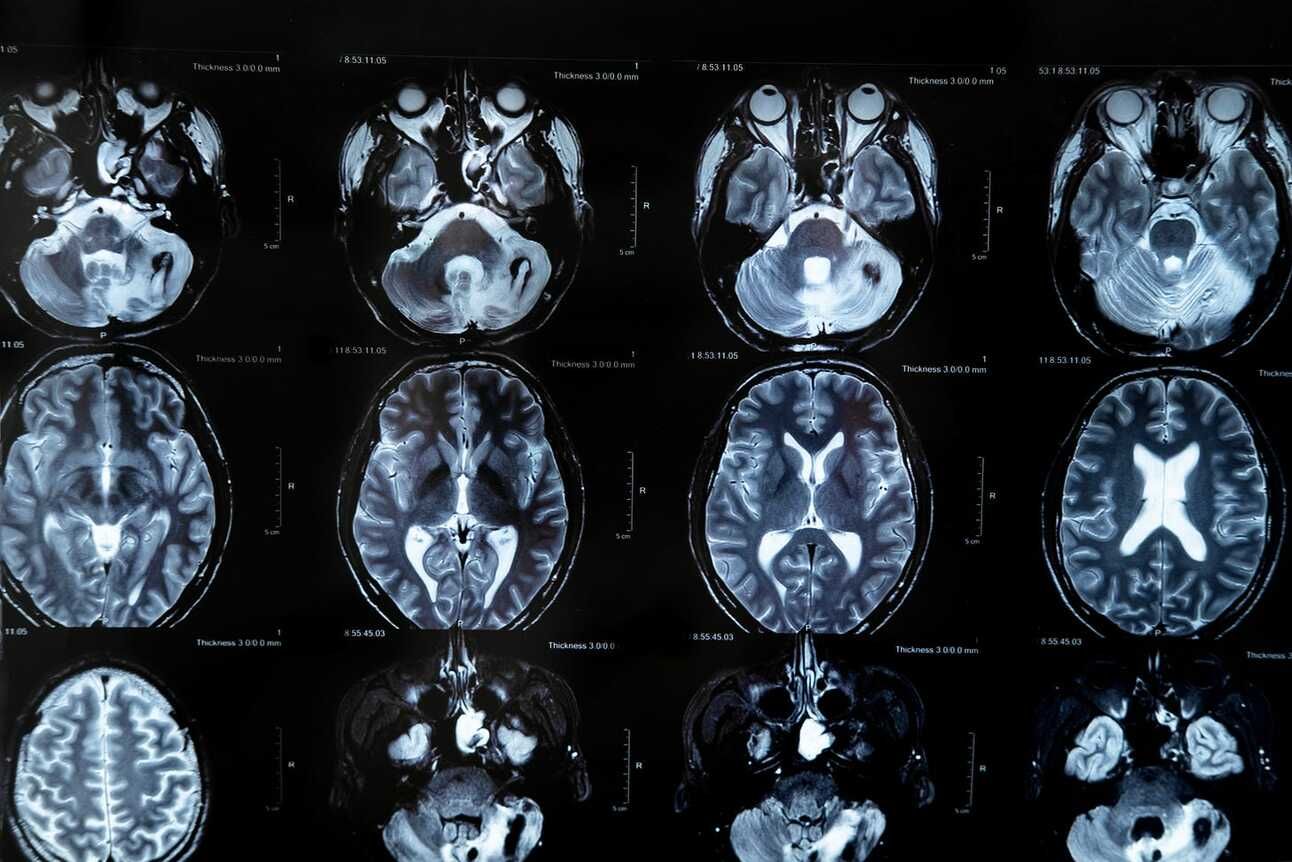

See Part 1 before diving in. We have downloaded the UPenn GBM MRI scans and the clinical data from TCIA. Let’s take a look at the clinical data to get an understanding of the patient cohort.

Each patient has an unique ID. Their Gender and Age at the time of the MRI scan is listed. If available, the number of Days they survived after surgery is shown. Some patients do not have this information listed as potentially the authors were not able to contact them or collect this information before the study ended. The next two fields show the mutational status of isocitrate dehydrogenase (IDH-1), and the presence of the O6-methylguanine-DNA-methyltransferase (MGMT) gene, both of which are strong biomarkers for GBM survival prognosis. We then have the Karnofsky Performance Status (KPS) score. This is a qualitative score from 0-100 that indicates the ability of the patient to perform daily activities and self-care. A KPS score of 0 means the patient is deceased. Taken together, this clinical data can help us train a survival model that can predict a patient's Overall Survival (OS).